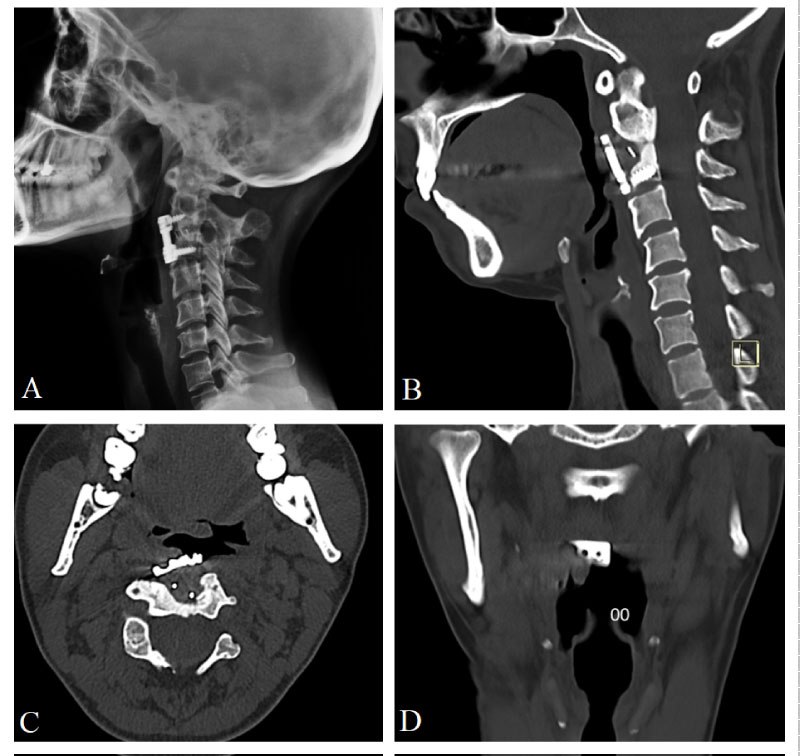

A 36-year-old female patient was admitted to our department with a diagnosis of traumatic listhesis at the C2-3 level after a motor vehicle accident. Neurological examination of the patient revealed no deficit. C2-3 anterior cervical discectomy, fusion with polyether ether ketone (PEEK) cage and anterior plate-screw fixation surgery were performed. After eight years from surgery, the patient presented to our clinic with dysphagia. On examination, she had a sore throat for the past few weeks and had a foreign body sensation in her throat. Fiber optics pharyngoscopy was used in physical examination, and mucosal erosion was seen in the oropharyngeal region. Anterior cervical plate was visible on the posterior wall of the pharynx (Figure 1A) and there was no appearance of abscess formation or inflammation. Cervical vertebra X-ray (Figure 2A) and CT (Figure 2B) revealed fusion at the C2-3 level, but also a perforation of the pharynx wall due to the fixation device (Figure 2C and Figure 2D). As the patient had adequate fusion, it was concluded that there was no need for re-stabilization surgery. Therefore, surgery was planned for removal of fixation device and repair of the pharyngeal wall. During surgery, the oral cavity did not allow manipulation with a screwdriver (Figure 1B). The margins of the pharyngeal mucosa in the perforation area were seemed to be healthy (Figure 1A). So, the anterior cervical approach was applied instead of transoral approach and fixation device was removed. Broad-spectrum antibiotics and total parenteral nutrition were used in the treatment of pharynx perforation, and the wound was left to healing with secondary intention. The patient was followed up in the hospital for two weeks. During this period the symptoms of dysphagia improved, and she was discharged. In 12 weeks after discharge, the primary repair of the pharynx with removal of fixation device was failed although any infection did not occur. Since the healing was insufficient despite 12 week-period and to prevent secondary infection, the otolaryngology team has repaired the pharyngeal perforation surgically by turning the mucosal flap. The patient is currently being followed up without symptom.

Figure 2: Lateral cervical X-ray. A) Showing adequate fusion at C2-3 level after eight years from ACSF; B) Sagittal; C) Axial; D) Coronal. Plane of cervical vertebra CT which was taken eight years after surgery, showing pharyngeal perforation and fixation device protrusion to pharyngeal cavity. View Figure 2